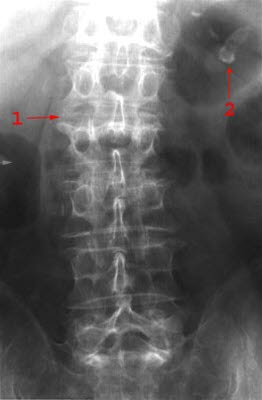

Columnafraktur frontalbilde

Kompresjonsfraktur med nedpressing av øvre dekkplate L2

Bifunn: Veggforkalkninger i miltarterie

- Øvre dekkplate L2

- Miltarterie